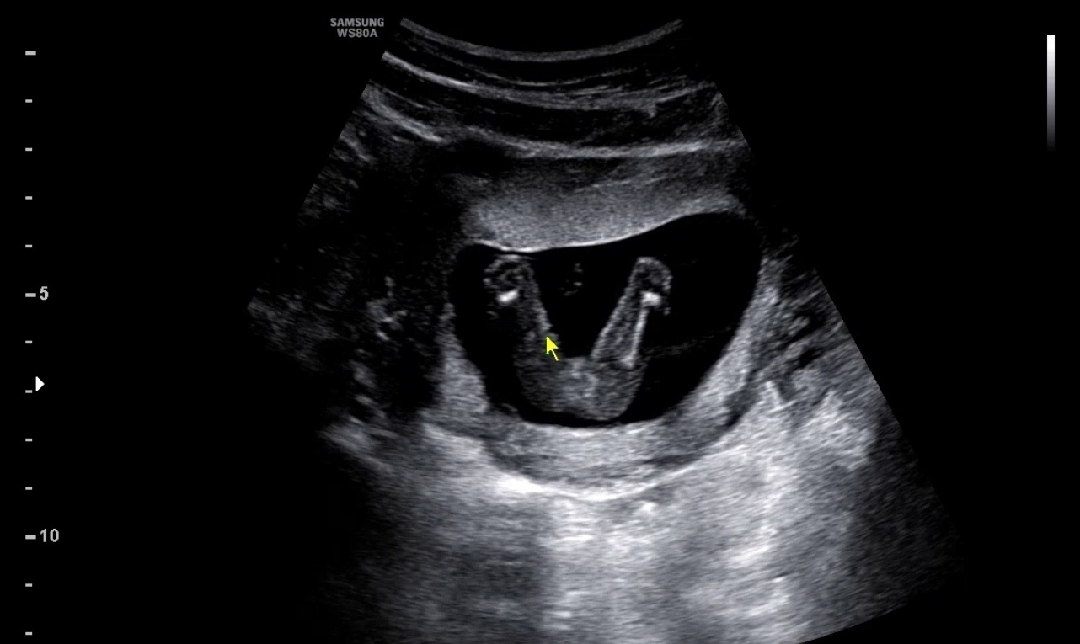

다리 너무 귀여워요 ㅋㅋㅋㅋ 캐릭터같아요

어제까진 진짜 아무렇지도 않았는데 오늘 병원에 갈 생각하니 괜히 긴장이 막 되는거에요ㅠㅠ 그래서 그런가 괜히 5시반에 인나서 뒤척뒤착 대다가 병원 다녀왔어요! 초음파 먼저 봤는데 이제는 애기 길이로 안 재고 머리둘레, 배둘레, 허벅지 길이로 잰다고 하시더라구요ㅋㅋ 둘레라니 뭔가 귀엽ㅠㅠㅠ 사실 아들딸 구별말고 건강하게만 나와다오ㅠㅠ 였지만! 그래두 궁금하잖아요 그쵸?!?! 영상 쭈욱 보시더니 핑크색에 가깝다고!! 다음에 더 정확해지겠지만 원장님두 보시고는 90퍼 이상 확정이라고!!! 너무 좋아하면 안된다고 어른들이 그러셨으니 여기까지ㅋㅋ 다음주에 나올 2차 기형아 검사 결과가 아직은 괜히 우려스럽지만 그래도 어차피 내 손을 떠난거 얌전히 기다려보겠습니다:) 여러분들도 화이팅!!🩷